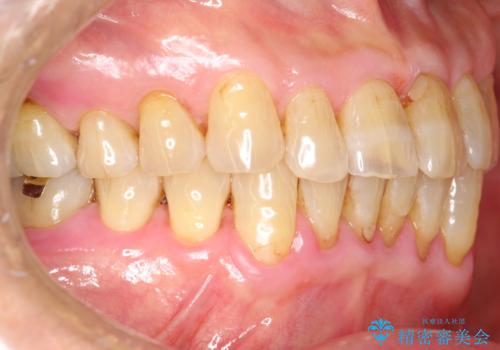

歯周病の治療前にまずはモチベーションUPにPMTCでステインの除去

担当医 歯科衛生士